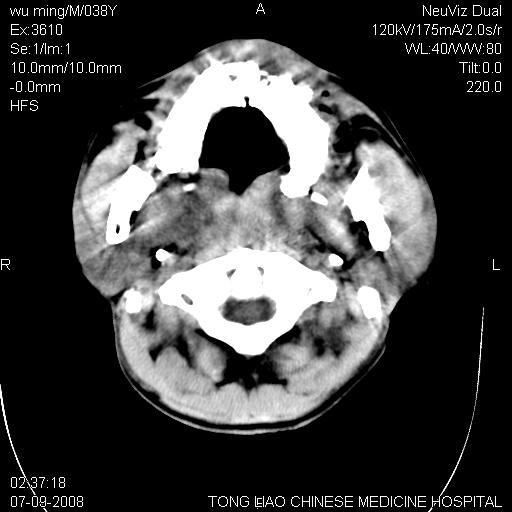

颅底多发骨折。

颅底多发骨折.

颅底多发骨折.上颌骨多发骨折

右侧眼眶,上颌骨,鼻骨、上颌窦等很多

考虑:面骨、颅底骨多发骨折,颅内高压(脑肿胀)。

面骨、颅底骨多发骨折,右侧硬膜下小血肿,弥漫轴索损伤,死亡原因可能是多种因素致。

1)颅底骨及颌面骨多发性骨折。2)副鼻窦及双侧鼻腔积血。

颅底骨折,窦腔内积血。考虑死亡原因为脑水肿压迫脑干或因大量失血死亡。